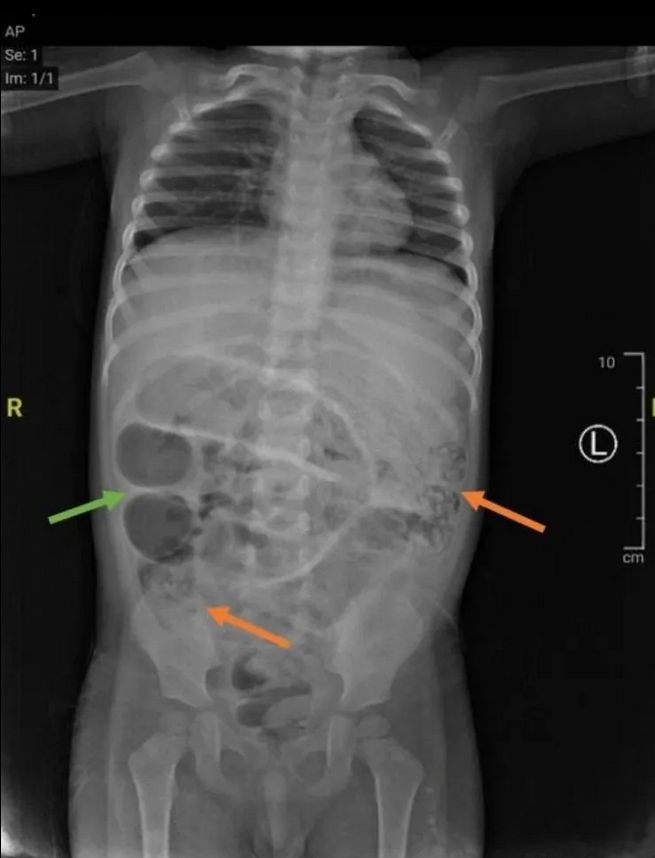

Dramatyczny przebieg leczenia opisano w dzienniku "Journal of Medical Case Reports". Chłopiec zaczął nagle wymiotować żywymi robakami. Po wykonaniu badań i prześwietlenia jamy brzusznej okazało się, że jego jelita były niemal całkowicie zablokowane przez pasożyty.

W czasie operacji chirurdzy usunęli robaki z trzech różnych miejsc jelita cienkiego. Badania wykazały, że chłopiec był zakażony glistą ludzką (Ascaris lumbricoides) - jednym z najczęstszych pasożytów jelitowych na świecie. Dorosłe osobniki tych robaków mogą osiągać nawet 35 cm długości i żyją w jelitach człowieka.

Badania ujawniły przyczynę dolegliwości

Badania ujawniły przyczynę dolegliwości © Journal of Medical Case Reports